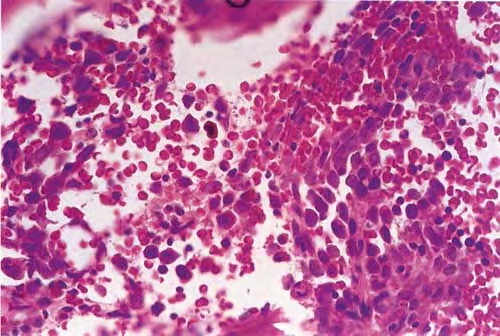

Read MoreAdenoid (acantholytic) scc = الكارسينوم شائك الخلايا الغداني منحل الاشواك